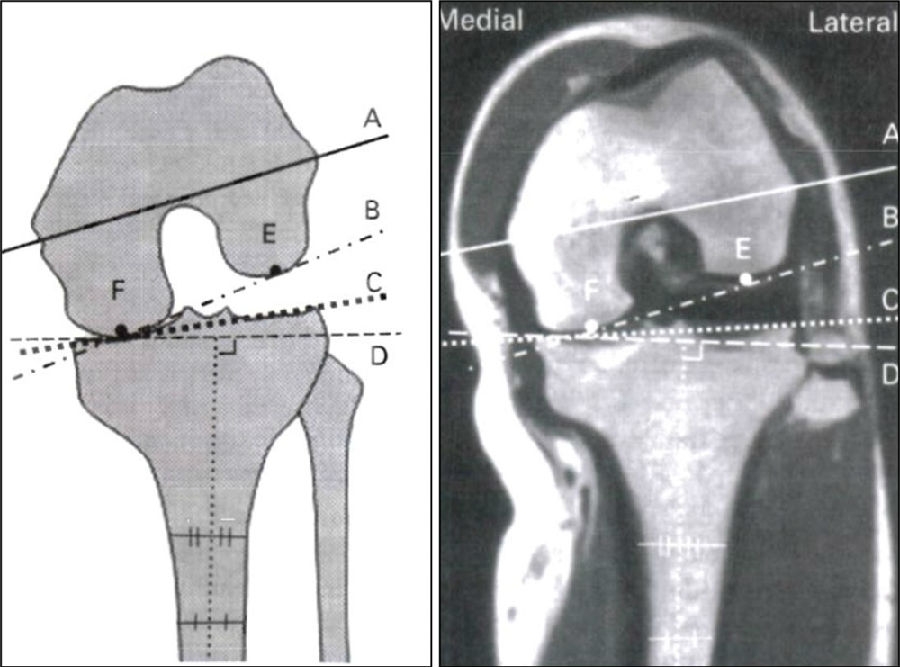

理想假体位置 A.股骨假体 胫骨假体中心线一致;B.股骨假体固定栓与后侧皮质呈35-40°

理想假体位置即前缘平稳过渡,后缘包容很好且不超出。